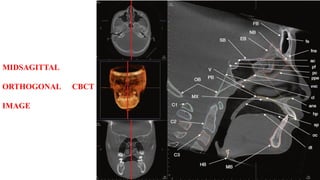

MIDSAGITTAL

ORTHOGONAL CBCT

IMAGE

SAGITTAL

Images in the sagittal orthogonal plane demonstrate a continuum of anatomy

extending from the midline of the nasal cavity and cranial base laterally to the

mastoid sinuses and glenoid fossa of the temporal bone and condylar head of the

mandible.